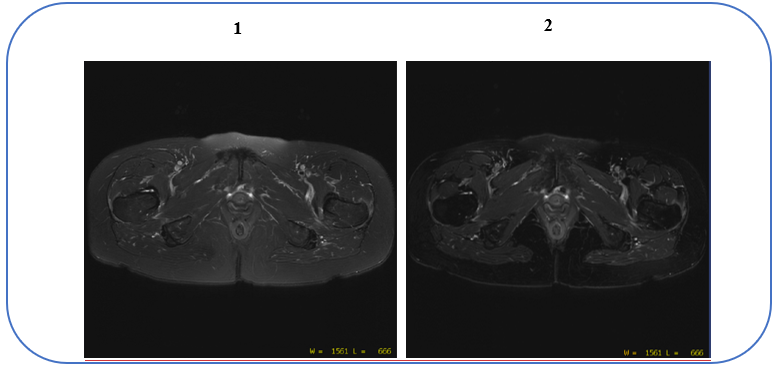

Figure 2. Real Time Center Frequency on/off affects on fat suppression

Table 1. Image legend Number Description 1 Image acquired with Real Time Center Frequency option turned Off. The arrows indicate the area of poor fat suppression.

2 Image acquired with Real Time Center Frequency option turned On. Note the improved fat suppression. - To reduce signal drop-off in areas of high B0 inhomogeneity (off-isocenter, or area with high tissue susceptibility).